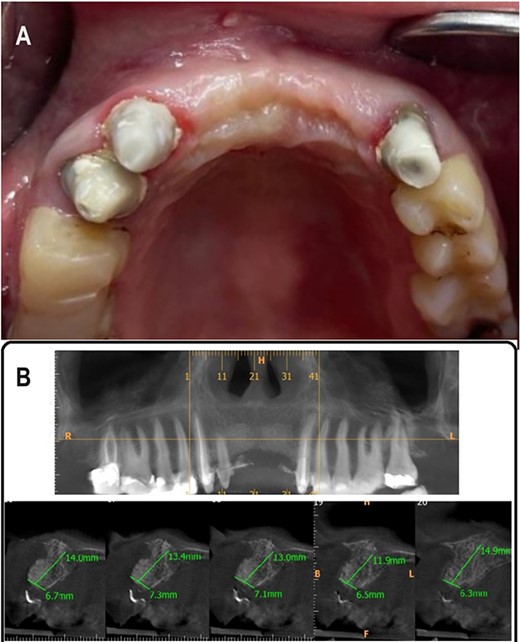

A 33-year-old medically fit female patient came to the dental care center suffering from missing teeth in the upper anterior region (11, 21, 22). During clinical and radiographic examinations, severe bone resorption was observed. Alveolar bone thickness ranged from 2.4 to 3.4 mm (Class IV according to Tolstunov classification for alveolar ridge defects [13]), (Fig. 1A and B) gingival thickness was moderate (1 mm). After discussing all treatment options with the patient, the treatment was planned in two stages. The first stage, horizontal bone augmentation using bone allograft in combination with C-PRF. The second stage, implant surgery after 5 months from the first stage.